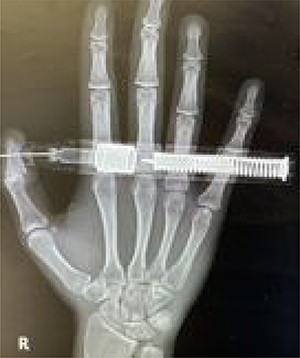

We successfully removed the embedded needle in a sterile manner through moderate countertraction (Fig. 3) and irrigation with 2 l of normal saline with povidone. The X-ray was repeated after removal to rule out the presence of any residual foreign bodies. The examination was repeated and the results showed a normal and intact thumb.